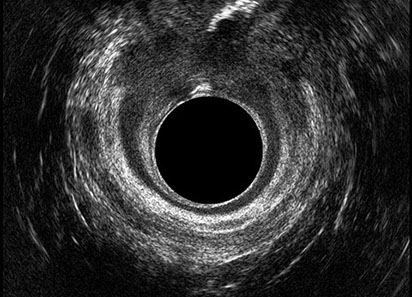

L’ecografia transanale è un esame diagnostico per immagini che consiste nell’introduzione di un trasduttore ad ultrasuoni. Le immagini qualitativamente migliori del canale anale sono ottenute usando un trasduttore rotante, montato in un manipolo rigido, che fornisce un’immagine a 360°. Con le apparecchiature più moderne è anche possibile ottenere immagini tridimensionali.

L’ecografia transanale permette di distinguere la sottomucosa che riveste il canale anale, lo sfintere anale interno, e lo sfintere anale esterno.

Le principali indicazioni all’esecuzione di tale esame sono lo studio dell’integrità delle strutture muscolari nei casi di incontinenza fecale, lo studio topografico dei processi settici perianali (ascessi e fistole) e lo studio dei processi proliferativi epiteliali (carcinoma anale).

Proctal dispone di apparecchiatura per ecografia endoanale 3D con sonda rotante.